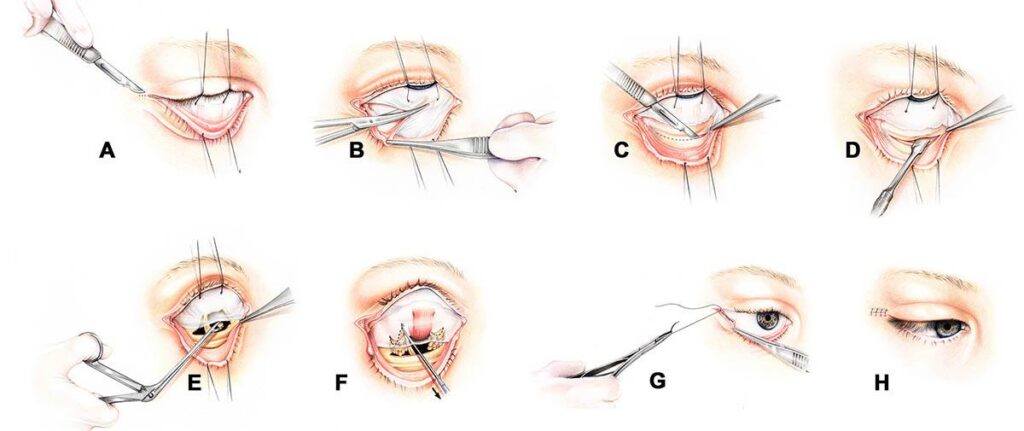

In active endocrine orbitopathy, treatment usually comprised of medical therapy (with certain drugs) and/or surgical treatment of the thyroid. Orbital decompression surgery, to relieve these issues, only becomes an option once the diseases has stopped progressing for a period of at least one year. Orbital decompression surgery involves removes bone from the eye socket so that the swollen eye muscles have more space to reside, and no longer push the eye forward. Clearly, this does not treat the underlying disease, but rather, but it can greatly improve a patient’s quality of life, as it ensures normal eyelid closure and also helps restore the patient’s own self-image: looking in the mirror and seeing a reflection of themselves with bulging eyes can be difficult to bear. There are a number of surgical techniques that can be used to achieve orbital decompression, performed by various specialists, including facial surgeons, ear, nose and throat surgeons and orbital surgeons. The latter are highly specialized eye surgeons who treat all diseases around the bony eye socket. There are several techniques that can be used to perform this surgery – and they differ in both approach and result. Most facial surgeons prefer “transantral” approach, in which the facial skin is released at the top of the skull and “folded” down, so that the eye socket is freely accessible. You can appreciate why we chose not to show illustrations of this approach on the website. Most orbital surgeons, including Dr. Dr. Paridaens, prefer access via the lower eyelid with a ~3 mm-long, hidden, cut. This has the benefit of much easier and faster wound healing, as the incision is far smaller than the transantral approach. Below are illustrations (© Dr. Dr. Paridaens) that show the different stages of orbital decompression surgery using his preferred approach via the lower eyelid. Read more…